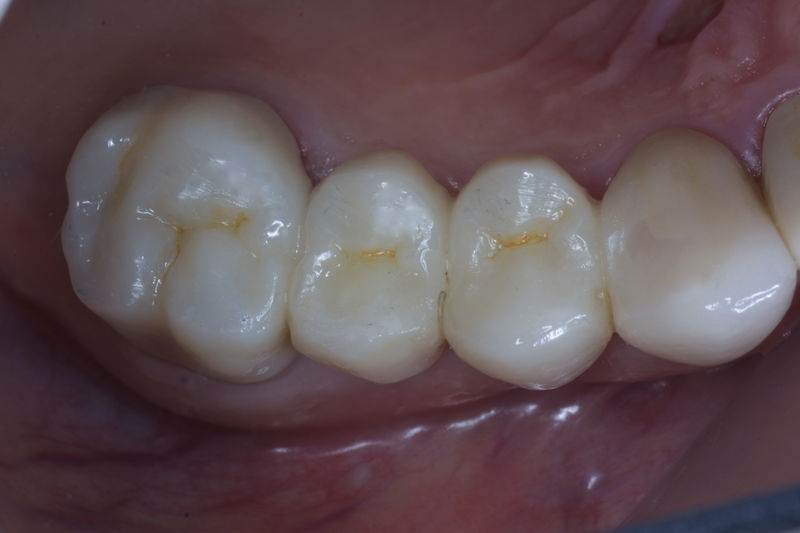

Restauraciones fabricadas en el laboratorio con materiales estéticos, los cuales cubren de manera parcial dientes posteriores. Se utilizan primariamente para restaurar dientes con caries, fracturas y/o defectos amplios. Para poder enviar el caso al laboratorio se toman impresiones utilizando materiales de impresión o técnicas modernas digitales.

Restauraciones fabricadas en el laboratorio con materiales estéticos, los cuales cubren de manera total dientes anteriores y posteriores. Se utilizan primariamente para restaurar dientes con caries, fracturas y/o defectos amplios, así como soportes de puentes. Para poder enviar el caso al laboratorio se toman impresiones utilizando materiales de impresión o técnicas modernas digitales.

Implante fracasado, extracción, carillas, coronas y prótesis fija.